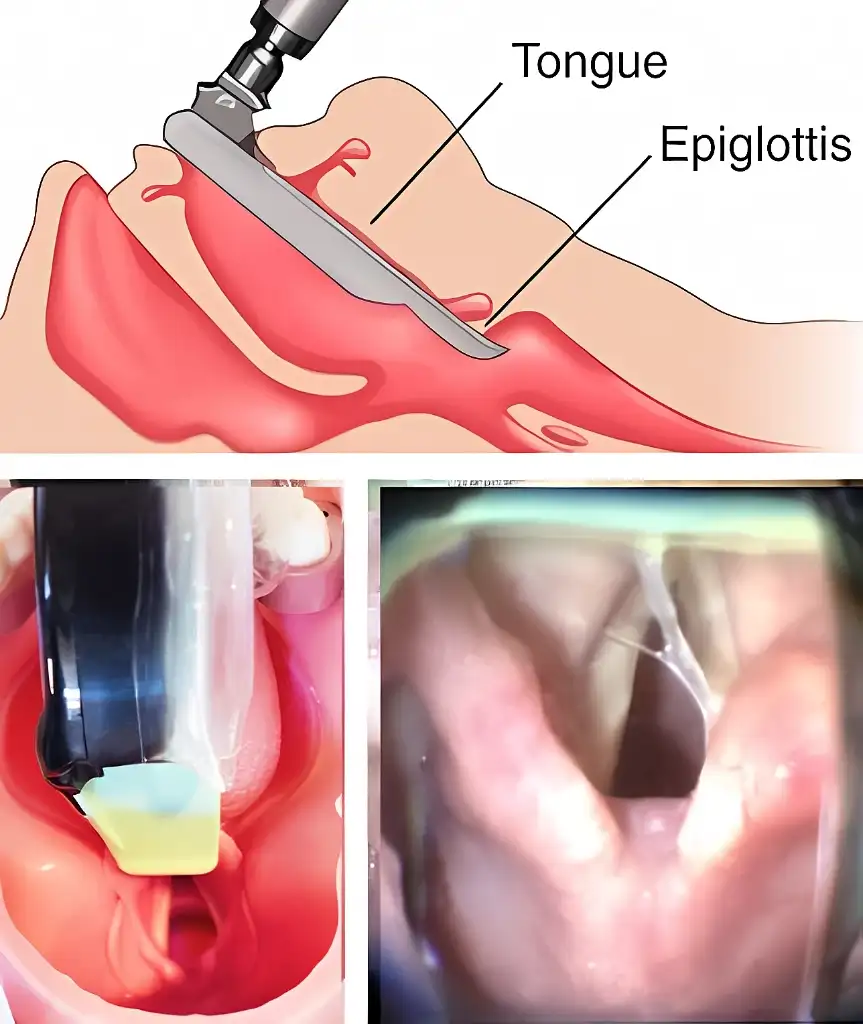

MacIntosh vs Miller

MacIntosh Blade in the Vallecula (preferred)

Airtraq allows both techniques

Macintosh style is the preferred option since it requires less upward traction and therefore it is softer on patient tissues.

If the Airtraq is already underneath the epiglottis and the user prefers to intubate Macintosh style withdraw the Airtraq until the epiglottis falls and advance the tip of the blade into the vallecula.

Miller Blade underneath Epiglottis